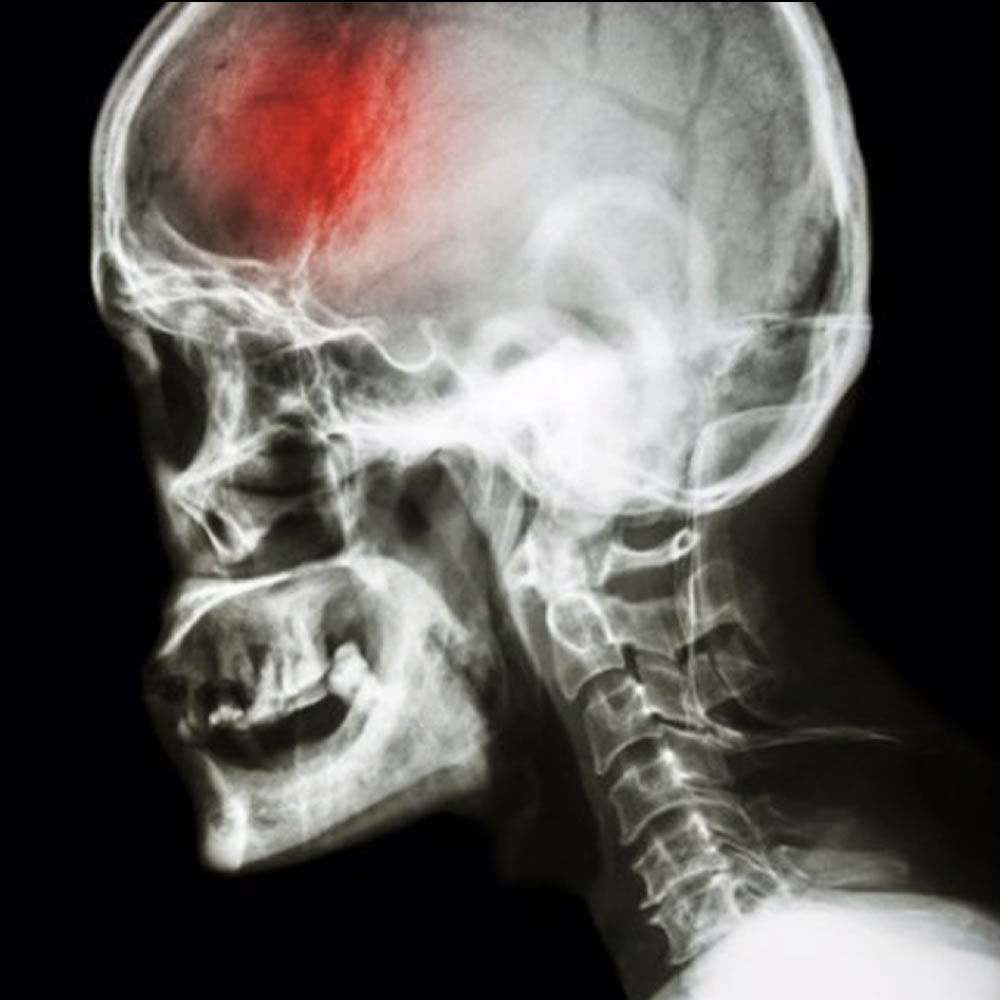

Las lesiones por traumatismo encéfalo-craneal varían dependiendo de múltiples factores (edad del paciente, mecanismo del trauma, área del trauma). Entre ellas, pueden presentarse fracturas craneo-faciales, hematomas intracraneales, edema cerebral, entre otras.

Es fundamental el estudio con neuroimágenes para determinar el compromiso craneo-cerebral y poder instaurar el mejor tratamiento.